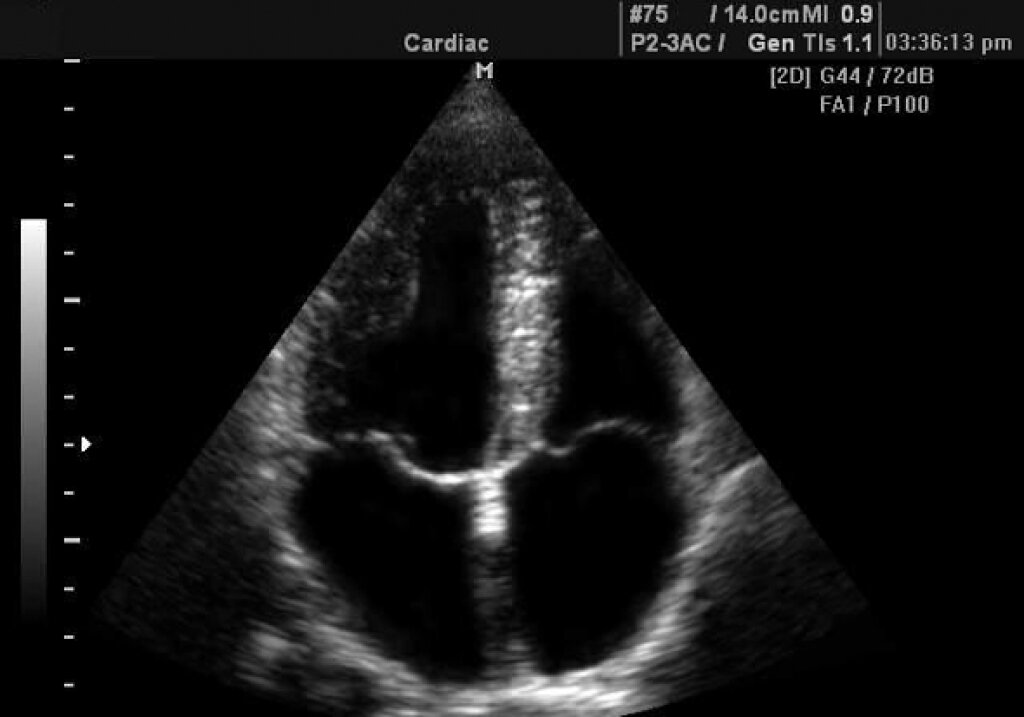

Эхокардиография (ЭхоКГ)  — метод ультразвукового исследования (УЗИ), направленный на исследование морфологических и функциональных изменений сердца и его клапанного аппарата. Если кратко, то его принцип основан на улавливании отражённых от структур сердца ультразвуковых сигналов.

Что позволяет оценить УЗИ сердца?

• толщину стенок сердца,

• состояние клапанного аппарата,

• объём полостей сердца,

• сократительную способность миокарда,

• оценить состояние аорты,

• оценить состояние перикарда,

• увидеть работу сердца в режиме реального времени,

• проследить скорость и особенности движения крови в предсердиях и желудочках сердца,

• увидеть пороки сердца, тромбы в сосудах,

• увидеть рубцы после инфаркта,

• увидеть новообразования,

• увидеть аневризмы,

• увидеть местоположение и состояние стентов и шунтов.